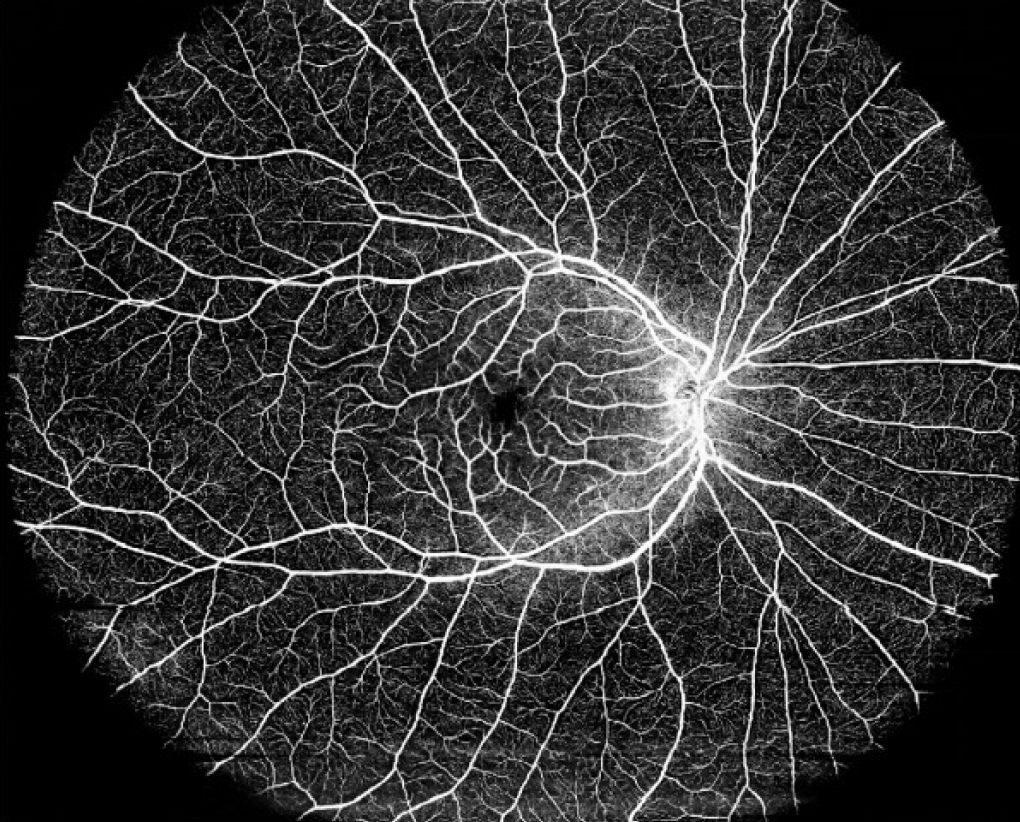

Bei einer OCT wird ein spezieller Scanner verwendet, der mithilfe von Lichtwellen die Netzhaut und andere Augenstrukturen in hoher Auflösung abbilden kann. Das Licht wird in das Auge gesendet, wo es von den verschiedenen Gewebeschichten reflektiert wird. Die reflektierten Lichtwellen werden dann vom Scanner erfasst und in ein digitales 3D-Bild (Tomografie) umgewandelt. Das akustische Pendant dazu ist die Sonographie.

- Hohe Auflösung: Die OCT liefert detaillierte Bilder der Augenstrukturen in hoher Auflösung.